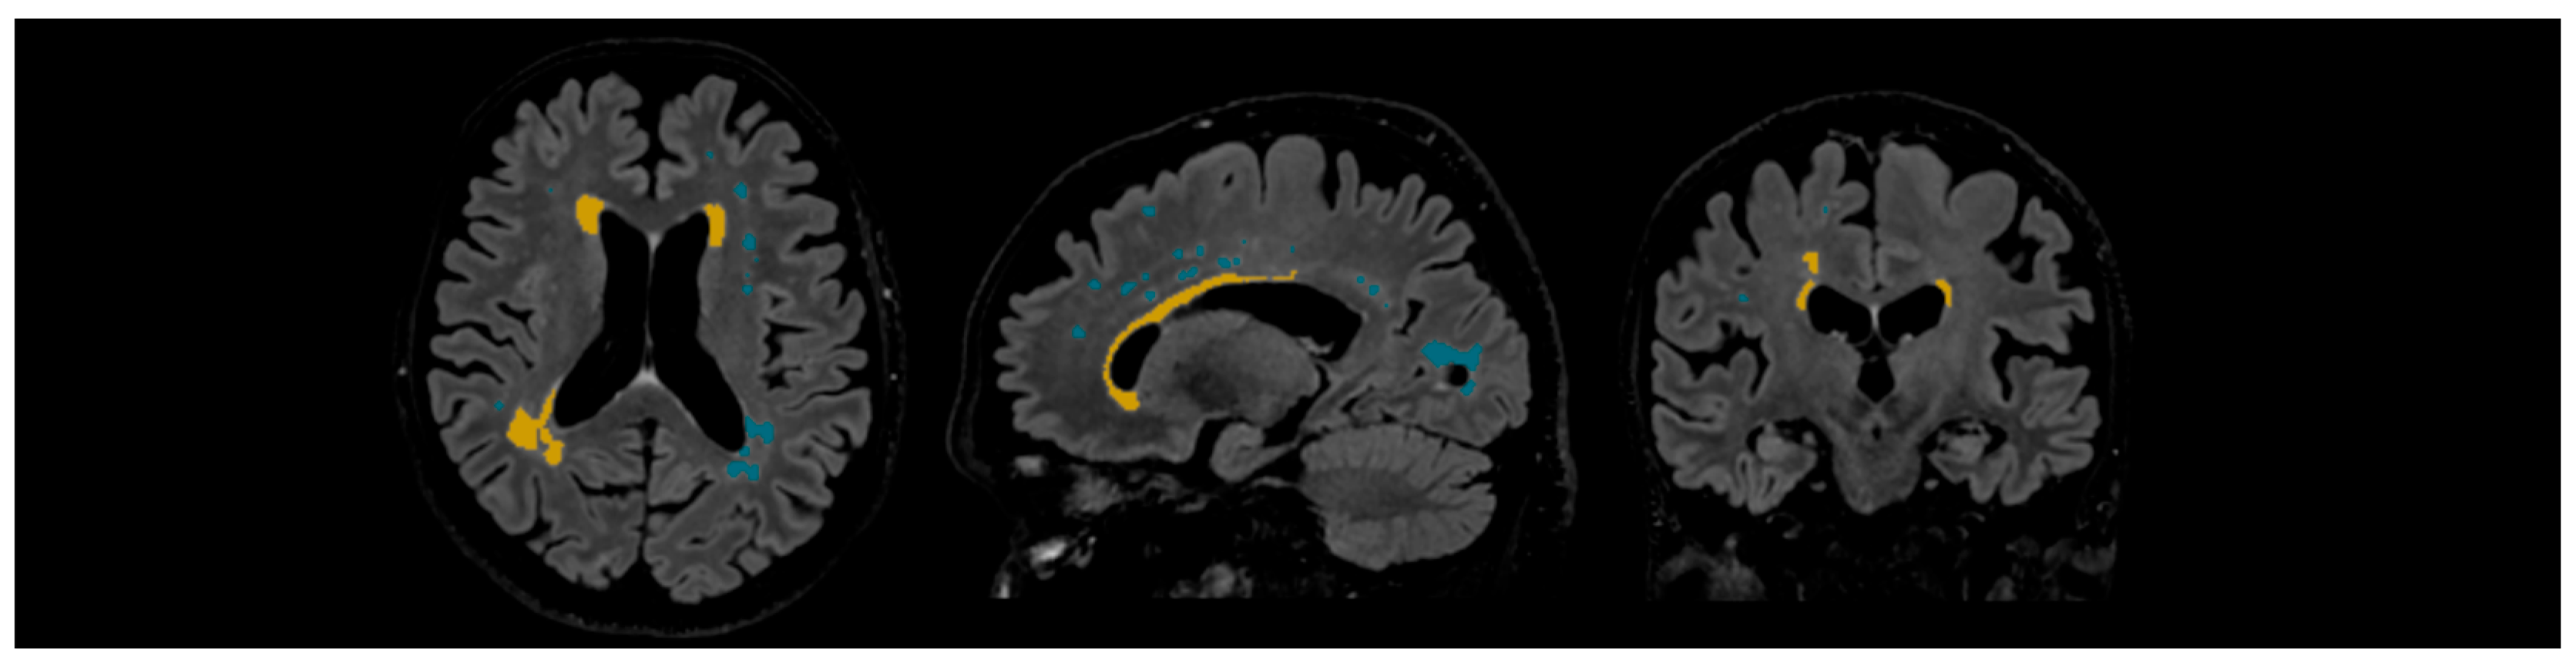

WMHs were quantified and delineated using Icometrix software (icobrain tbi report for MRI, version 5.12.0; Leuven, Belgium). The software identifies and evaluates WMHs by total volume and further categorises the lesions based on their anatomical regions (subcortical, periventricular, brainstem, and cerebellum), displaying volume values for each region. The software evaluates the volume of the whole brain, cortical grey matter, and the hippocampus. Moreover, Icometrix software compares these values to age- and sex-normative references from population data; however, in this study, we focused on WMHs (see Figure 3) [29].

Figure 3. Example of automated lesion delineation in axial, sagittal, and coronal planes. Yellow colour—periventricular white matter hyperintensities; blue colour—subcortical white matter hyperintensities.